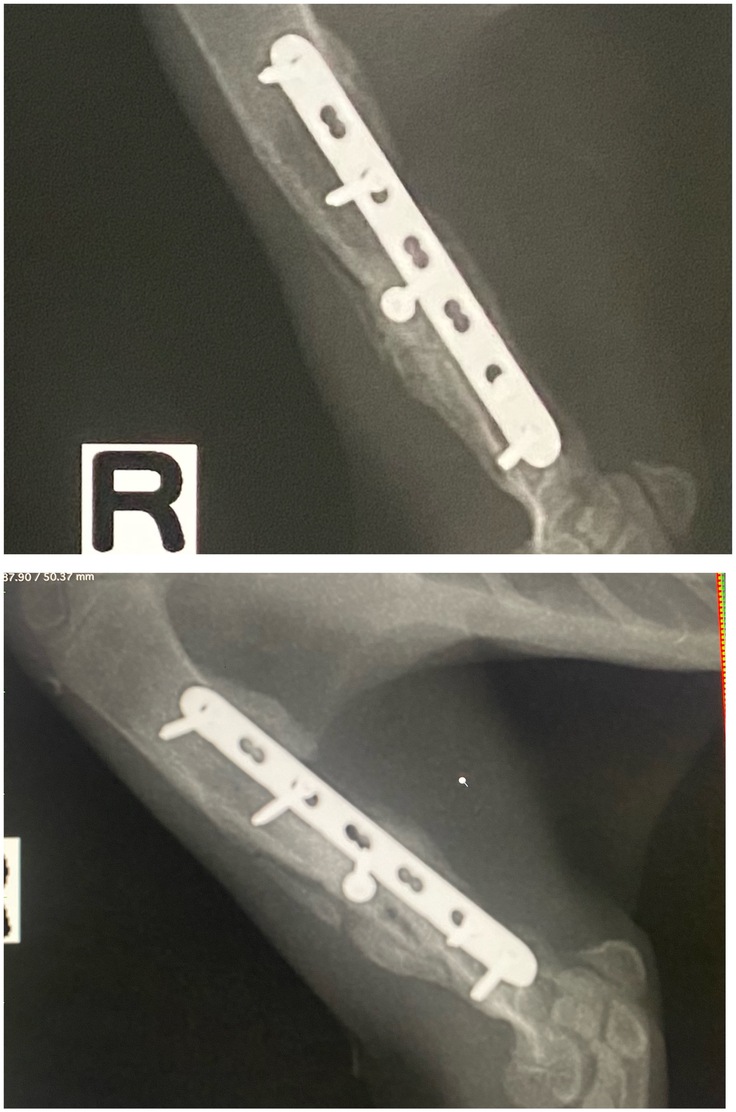

レントゲンの結果、骨がしっかりくっついたとの事でそのままプレートを外す手術のために入院となりました。

右前足

左後足

前回とくらべてゴツゴツした感じがなくなりました。古い骨が吸収され新しい骨が形成されていきます。膝より下も骨が伸び、タビちゃんもしっかり成長しています。